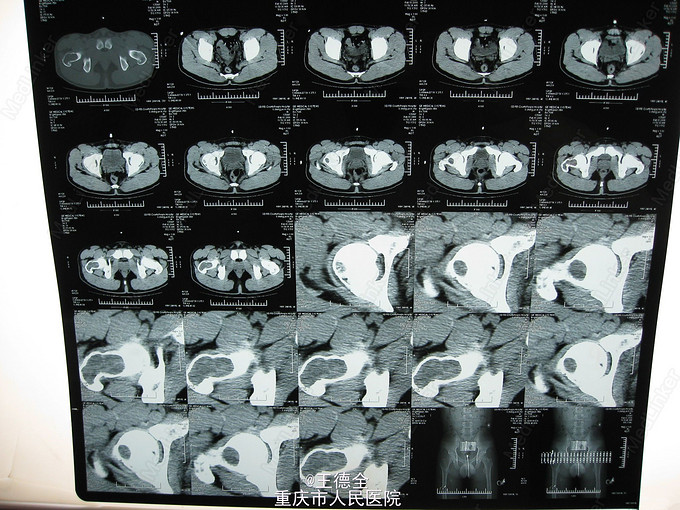

右股骨近端骨巨细胞瘤

患者男,21岁,因右髋部活动时疼痛3周入院,自诉既往无外伤史;查体:右髋部局部压痛,无红肿热痛,右髋关节活动可,右”4“字试验(+),右下肢肌力感觉正常。入院后完善相关检查,积极行病灶清除自体髂骨植骨伽马钉内固定术。